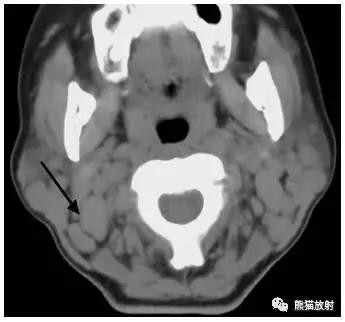

女性,45岁,淋巴瘤。(A)黑箭显示双侧IB区淋巴结,白箭显示ⅡA区淋巴结。(B)白箭显示ⅠA区淋巴结,黑箭显示左侧Ⅴ区淋巴结。

女性,45岁,淋巴瘤。黑箭显示双侧ⅡB区淋巴结。